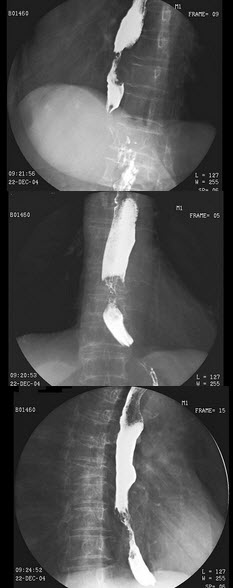

46、单项选择题

女,77岁,进行性吞咽困难月余,伴胸闷气短,腹胀。结合图像,最可能的诊断为()

B.右上肋间隙变窄

C.右肺门影增大